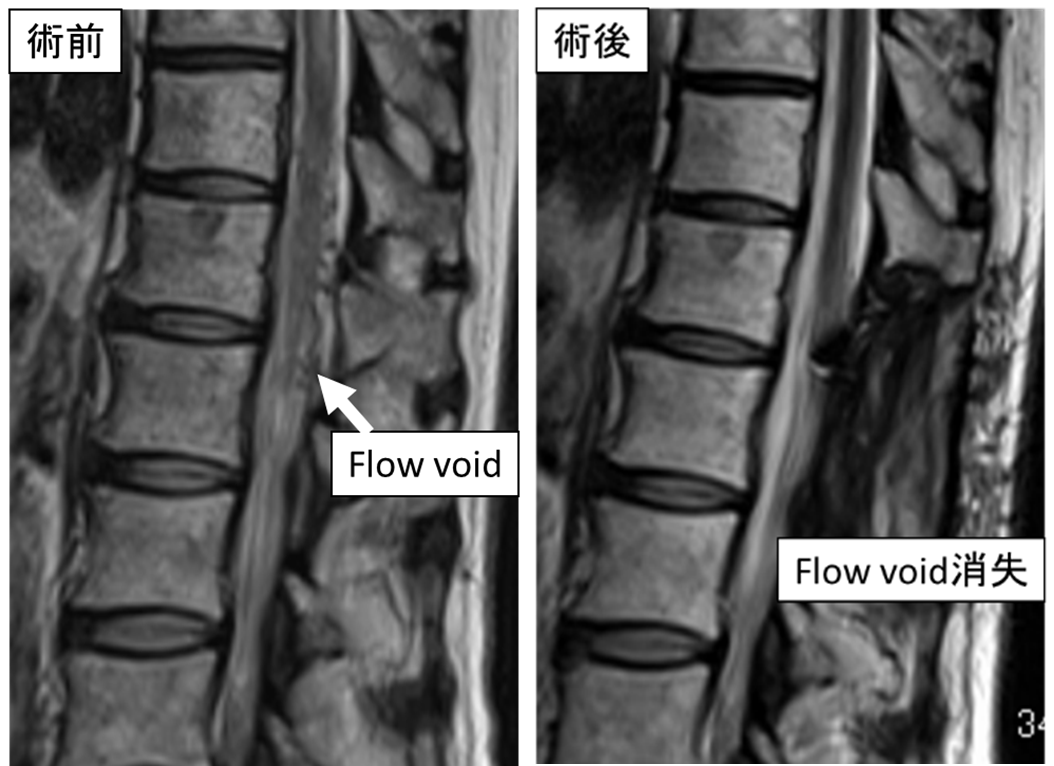

両下肢の脱力による歩行障害に対し脳外科医師

と協力し手術を行っています。術後しびれは残存

していますが、独歩可能です。